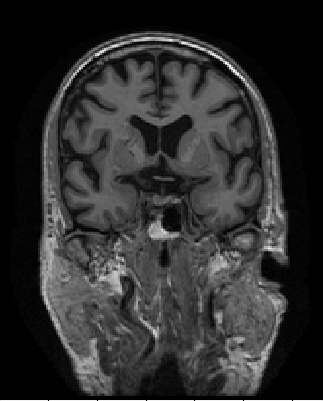

Refer to captionRefer to captionRefer to caption

(a) The axial, coronal, and sagittal view of the “preprocessed” scans.

(b) The axial, coronal, and sagittal view of the FreeSurfer post-processed scans.

(c) The 52nd axial, 92nd coronal, and 58th sagittal view of the brain extraction outputs from Clinica, which we used for 2D classification.

Figure 2: Slices from “preprocessed” scans, FreeSurfer post-processed scans, and the specific slices we use for 2D classification.

Furthermore, we extract 2D slices from fixed indices for each view of the spatially normalized brain extraction output. The indices were chosen based on visual prominence of the hippocampus of the brain. Specifically, they were the 52nd slice of axial view, the 58th slice of sagittal view, and the 92nd slice of coronal view. We also experimented with using neighboring slices for classification. Figure 2 shows the 2D slices of the brain extraction output by Clinica.